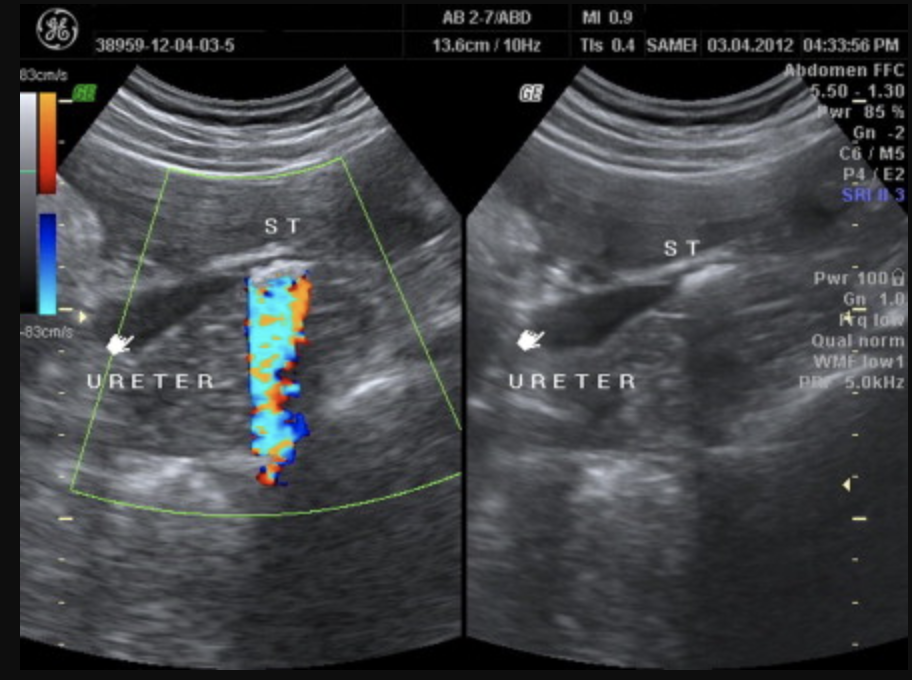

Which artefact may be used to help identify calculi?

Twinkling artefact -> distal to calculus using colour doppler